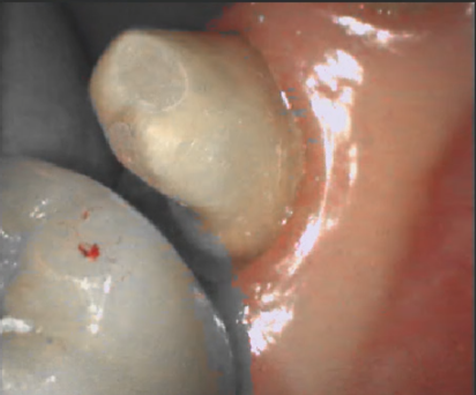

| 올바르지 않은 구강 환경 | 올바른 구강 환경 |